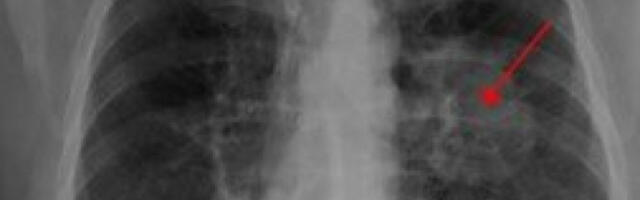

REVOLUCIJA: Veštačka inteligencija može RANIJE da otkrije rak pluća, evo i kako

Naučnici su naglasili da su prošla istraživanja dijagnostike raka pluća pokazala da se šanse za preživljavanje povećavaju ako se lečenje započne bar četiri nedelje ranije Pročitaj više